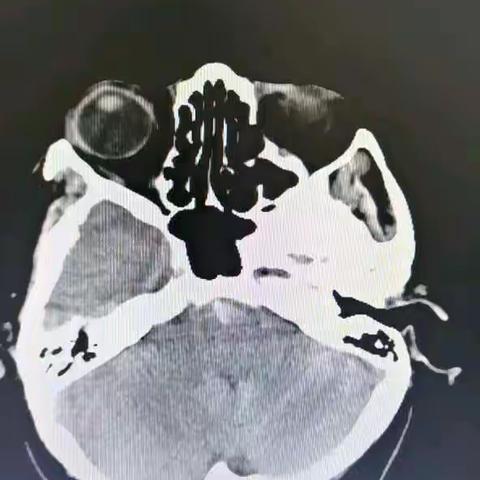

基底动脉极重度狭窄的破裂大脑后动脉动脉瘤栓塞术

左侧小脑前下动脉中段动脉瘤出血介入手术一例

两次破裂出血的右颈内动脉眼动脉段血泡样动脉瘤栓塞治疗一例----浙一医院 潘剑威 范卫健

右侧海绵窦区硬脑膜动静脉瘘经静脉栓塞一例----浙江大学医学院附属第一医院神经外科 潘剑威 范卫健

左侧颈内动脉慢性闭塞一例----潘剑威,范卫健

右颈内动脉次全闭塞开通一例----潘剑威 范卫健

左侧大脑后动脉P3分叉部动脉瘤一例----潘剑威 范卫健

第一例独立使用血流导向装置治疗海绵窦段巨大动脉瘤------浙一医院神经外科介入团队 潘剑威 范卫健

外伤性颈内动脉海绵窦瘘一例

LVIS辅助弹簧圈栓塞右颈内C6动脉瘤一例

81岁海绵窦区硬脑膜动静脉瘘